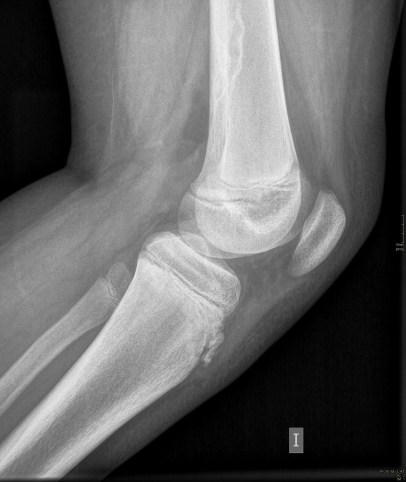

Cuando terminé la exploración y el radiólogo la chequeó le pidió al paciente unas placas para demostrar estos hallazgos, el resultado de las radiografías son estos, se aprecia perfectamente en la lateral los cambios o hallazgos que mostraba la ecografía MSK, mira:

Observa como en la espina tibial anterior, parece que el hueso se está despegando.

Como conclusión, podemos decir, una vez tenemos las imágenes de ambas técnicas que el diagnóstico de estos hallazgos radio-ultrasonográficos es la existencia de irregularidad a nivel de la tuberosidad tibial izquierda con engrosamiento de la porción insercional del rotuliano y cambios inflamatorios en partes blandas adyacentes.

Hallazgos que junto con los visualizados en RX son compatibles con enfermedad de Osgood-Schlatter.